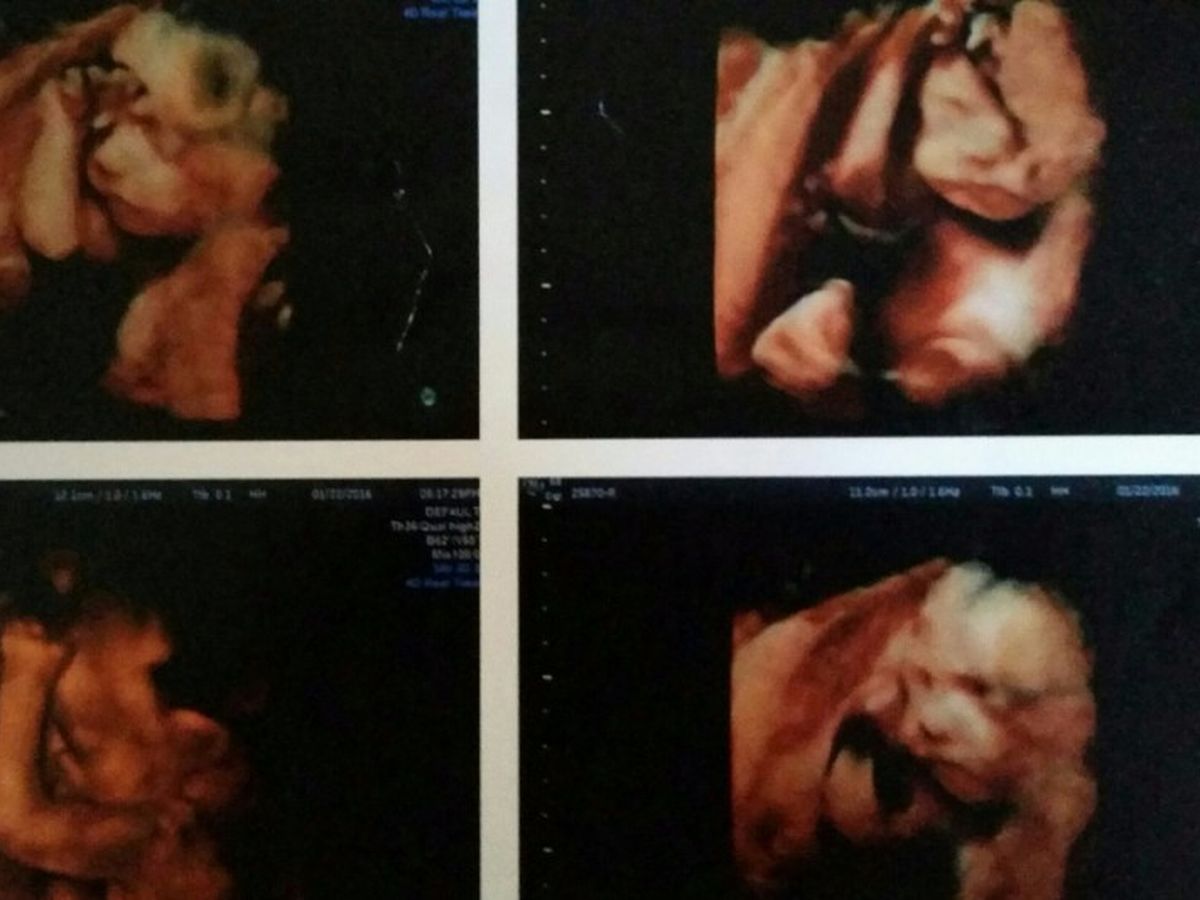

My wife and I are both on our second marriage, we wanted so badly to have a child together. She has three children and this would be my first child. After four miscarrages we went to a fertility clinic for testing. We were told that "it would take a miracle for us to have a child and that we would keep miscarring". We gave up, but to our surprise five months later Tamara was pregnant. Daily we were just waiting to miscarry. Each week that went by gave us a glimer of hope. At ten weeks we had a genetics screening test with a 99% accuracy. We were told that we were going to have a healthy little boy! We began to plan and named him after both of our fathers. Tamara's late father "Steven" and my families carried on name "James" which he would be a fourth generation. As days went on we started preparing for his arrival. Even got him his first Christmas ornament with his name on it.

All doubts were fading away as we got further and further along we were getting extremely excited thinking this was actually happening. At the twenty week anatomy scan we were told that everything was looking normal and fine, except the doctor saw a cyst on the umbilical cord but not to worry. But to be on the safe side our doctor sent us to see a specialist just for precautionary measures. At this point we weren't that worried since everything had been going well and earlier tests were all good. But little did I know at the next appointment that it was going to be one of the worst days of my life. We had a team of doctors come in and explain that there were more problems they were seeing along with the cyst. They also found cysts on his brain and holes in his heart. They strongly recommend we do more testing right away. So we did.

Now we are at thirty weeks, and after seeing several specialist. If he makes it to birth, their prediction is we may have minutes to a few days to spend time loving our new beautiful son.